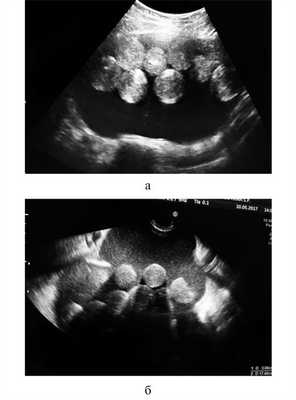

Необычными оказались результаты УЗИ органов малого таза. Матка визуализирована смещенной книзу, с четкими, ровными контурами, размером 35×31×33 мм, структура миометрия — однородная, М-эхо — 10 мм, соответствовало фазе менструального цикла (день менструального цикла на момент исследования 12-й). Шейка матки — 28×24 мм, обычного строения, канал шейки матки не расширен. Левый яичник — 41×27×31 мм, с мелкими фолликулами. В проекции правого яичника визуализировано объемное образование, выходившее из малого таза, занимавшее практически всю брюшную полость до гипогастрия. Контуры образования четкие, ровные, размер 190×100×180 мм, содержимое гетерогенное со взвесью и множественными округлыми гиперэхогенными образованиями внутри. Участков избыточной васкуляризации не выявлено. Имелось небольшое количество («следы») «свободной» жидкости в малом тазу. Заключение: объемное образование малого таза и гипогастрия, вероятнее всего, исходящее из правого яичника (Тератома? Паразитарная киста?) (рис. 1). Рис. 1. Эхографическая картина новообразования (а, б — различные сечения). Видны свободно плавающие в кистозной полости гиперэхогенные «шары» примерно одинакового строения и диаметра, на основании чего заподозрено наличие паразитарной инвазии.